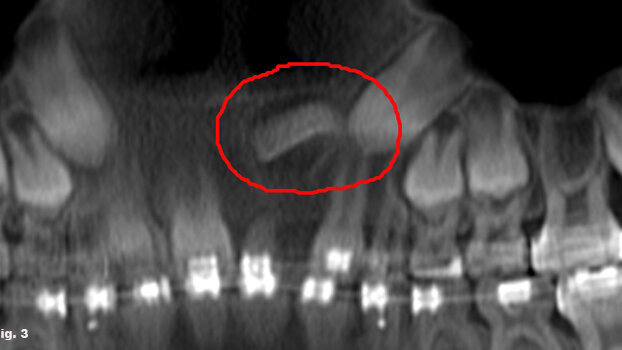

Our Cone Beam also gave us a great view of another patient’s horizontally impacted maxillary central incisor [Fig. 3]. When treatment started, the i-CAT machine aided the oral surgeon in exposing and placing a gold chain on the central for guided eruption. Her impacted canine, detected on the previous scan, has also since been brought into place.